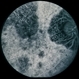

- Imaging device

Fundus camera

Optos Tx-200

- Fluorescein angiography montage of the right eye of a 56-year-old male with Bietti's crystalline dystrophy demonstrating advanced chorioretinal atrophy.